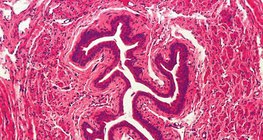

顯微鏡下的輸尿管橫切面